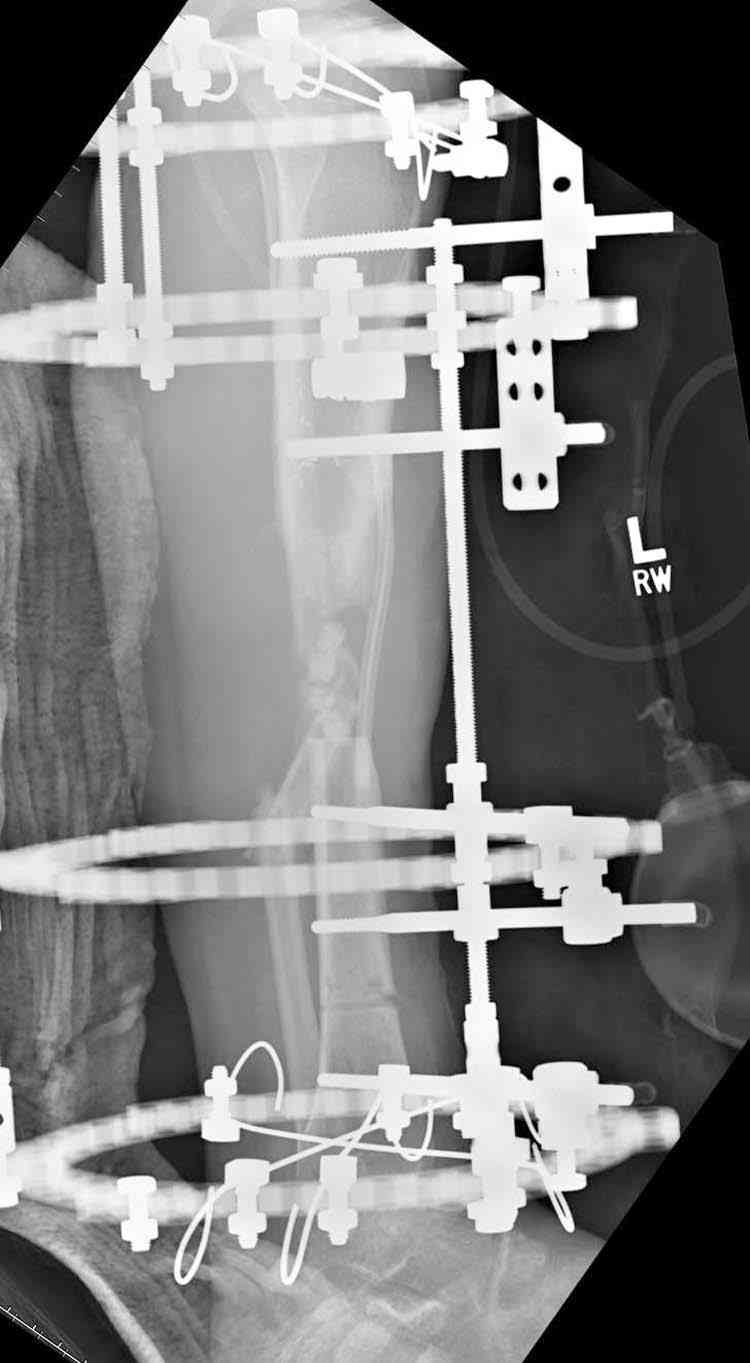

Согласен с тобой, короткий дистальный фрагмент, нет места ни для штифта, ни Т-образной пластины, да и шурупы мешают.

Конечно, возможность костной пластики не снимается, хотя из-за огромного дефекта имеется опасность плохого приживления, поэтому рекомендую приподнять блокированную мышечную пластику,

сделать поперечную остеотомию диафиза, полость заполнить antibiotic beads и начать удлинение.

Из аппаратов предпочтительно циркулярный, на дистальном фрагменте можно увеличить количество спиц.

Интересный случай, надо стараться сохранить сустав, любые осложнения грозят потерей части движений в суставе. При ведении сложных околосуставных дефектов не мешает предварительная моральная подготовка пациента к артродезу.

Здесь случай, хотя не тот уровень, но принцип "удлинения после заполнения дефекта Antibiotic Beads" сохранен, можно немного увеличить количество бус.